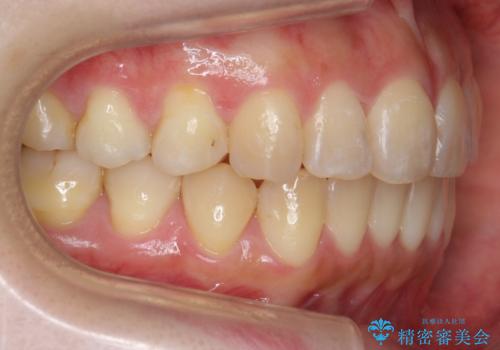

前歯を引っ込めたい 歯を抜かずにマウスピースで

- 前歯の突出を主訴に来院。

上の奥歯を後ろに下げて治療をしました。

矯正用のミニスクリューを使用しています。

上の前歯もIPR(エナメル質をわずかに削る処置)を行っています。